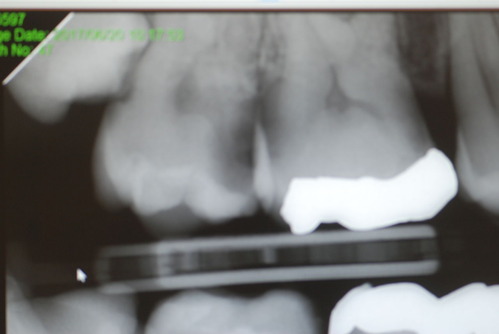

写真は典型的な取り残したまま銀歯を入れていた方のものです。よくぞ痛くならなかったものです。

意外と手間取り一時間以上かかりセメントを入れてとりあえず終了いたしました。神経が近いので傷つけて損傷すると助かる見込みが少なくなり、痛みが出て死んでしまうとか膿んでしまうこともあるのです。![570b1c06-s[1]](https://livedoor.blogimg.jp/netdental/imgs/6/0/60221eb2.jpg)